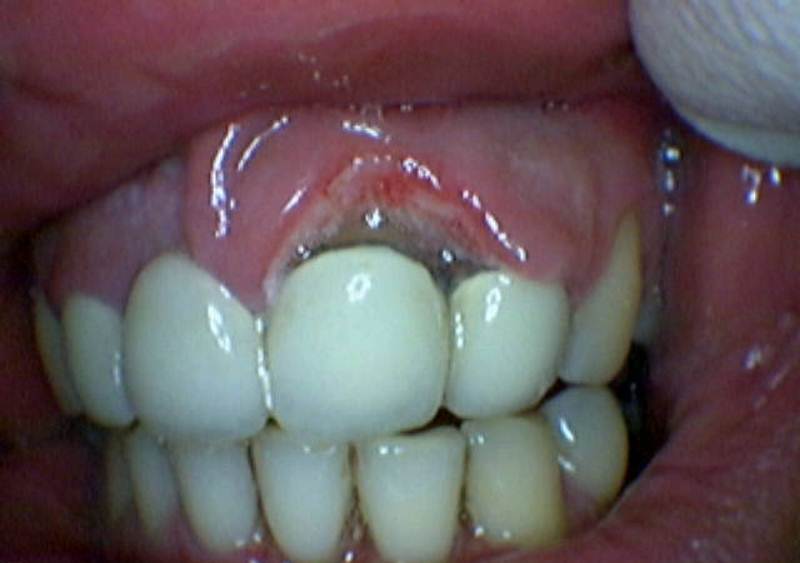

Главная Стоматит Как выглядит стоматит Стоматит на десне

Стоматит на десне

Полный размер 800 × 563 пикселей Как выглядит стоматит